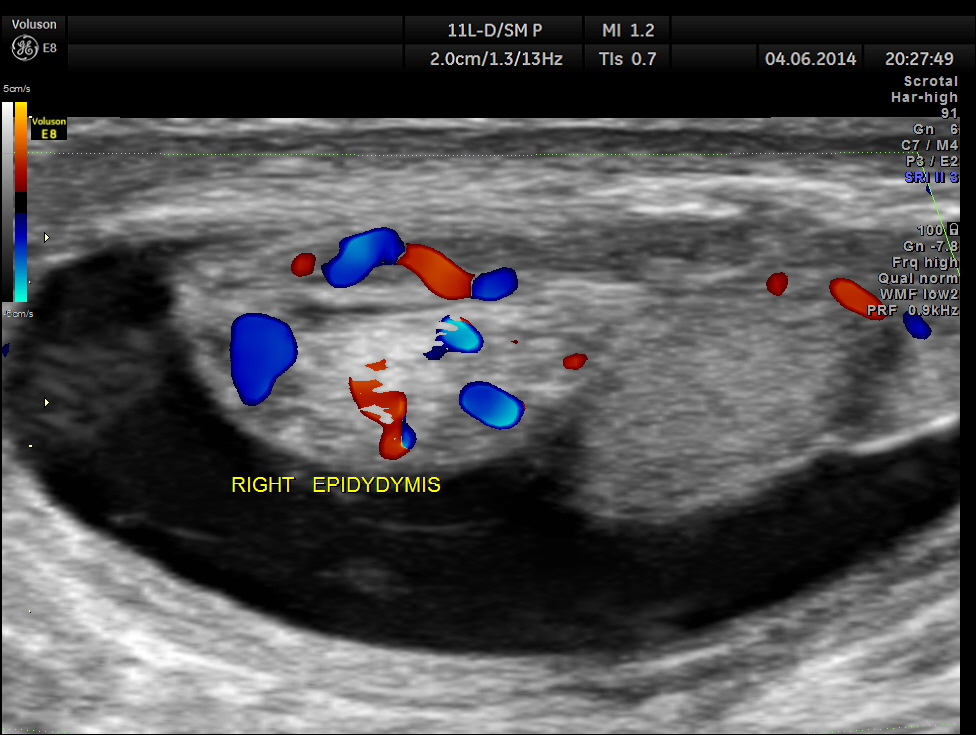

This was a 9-year-old boy , who was referred for evaluation of acute right scrotal pain of 2 days onset. He had mild right scrotal swelling and severe pain . One of the best uses of colour Doppler is for evaluation of acute scrotal pain , when the surgeon wants to rule out acute torsion . The other common condition is acute inflammation , which is medically managed. The images with colour just tell the story .

Rt Testis has normal appearance , with enlargement of the right epididymis . Colour flow imaging shows normal flow in the scrotum and increased flow in the epididymis , suggestive of acute inflammation – Acute Epididymitis.

Mild hydrocele is also seen.